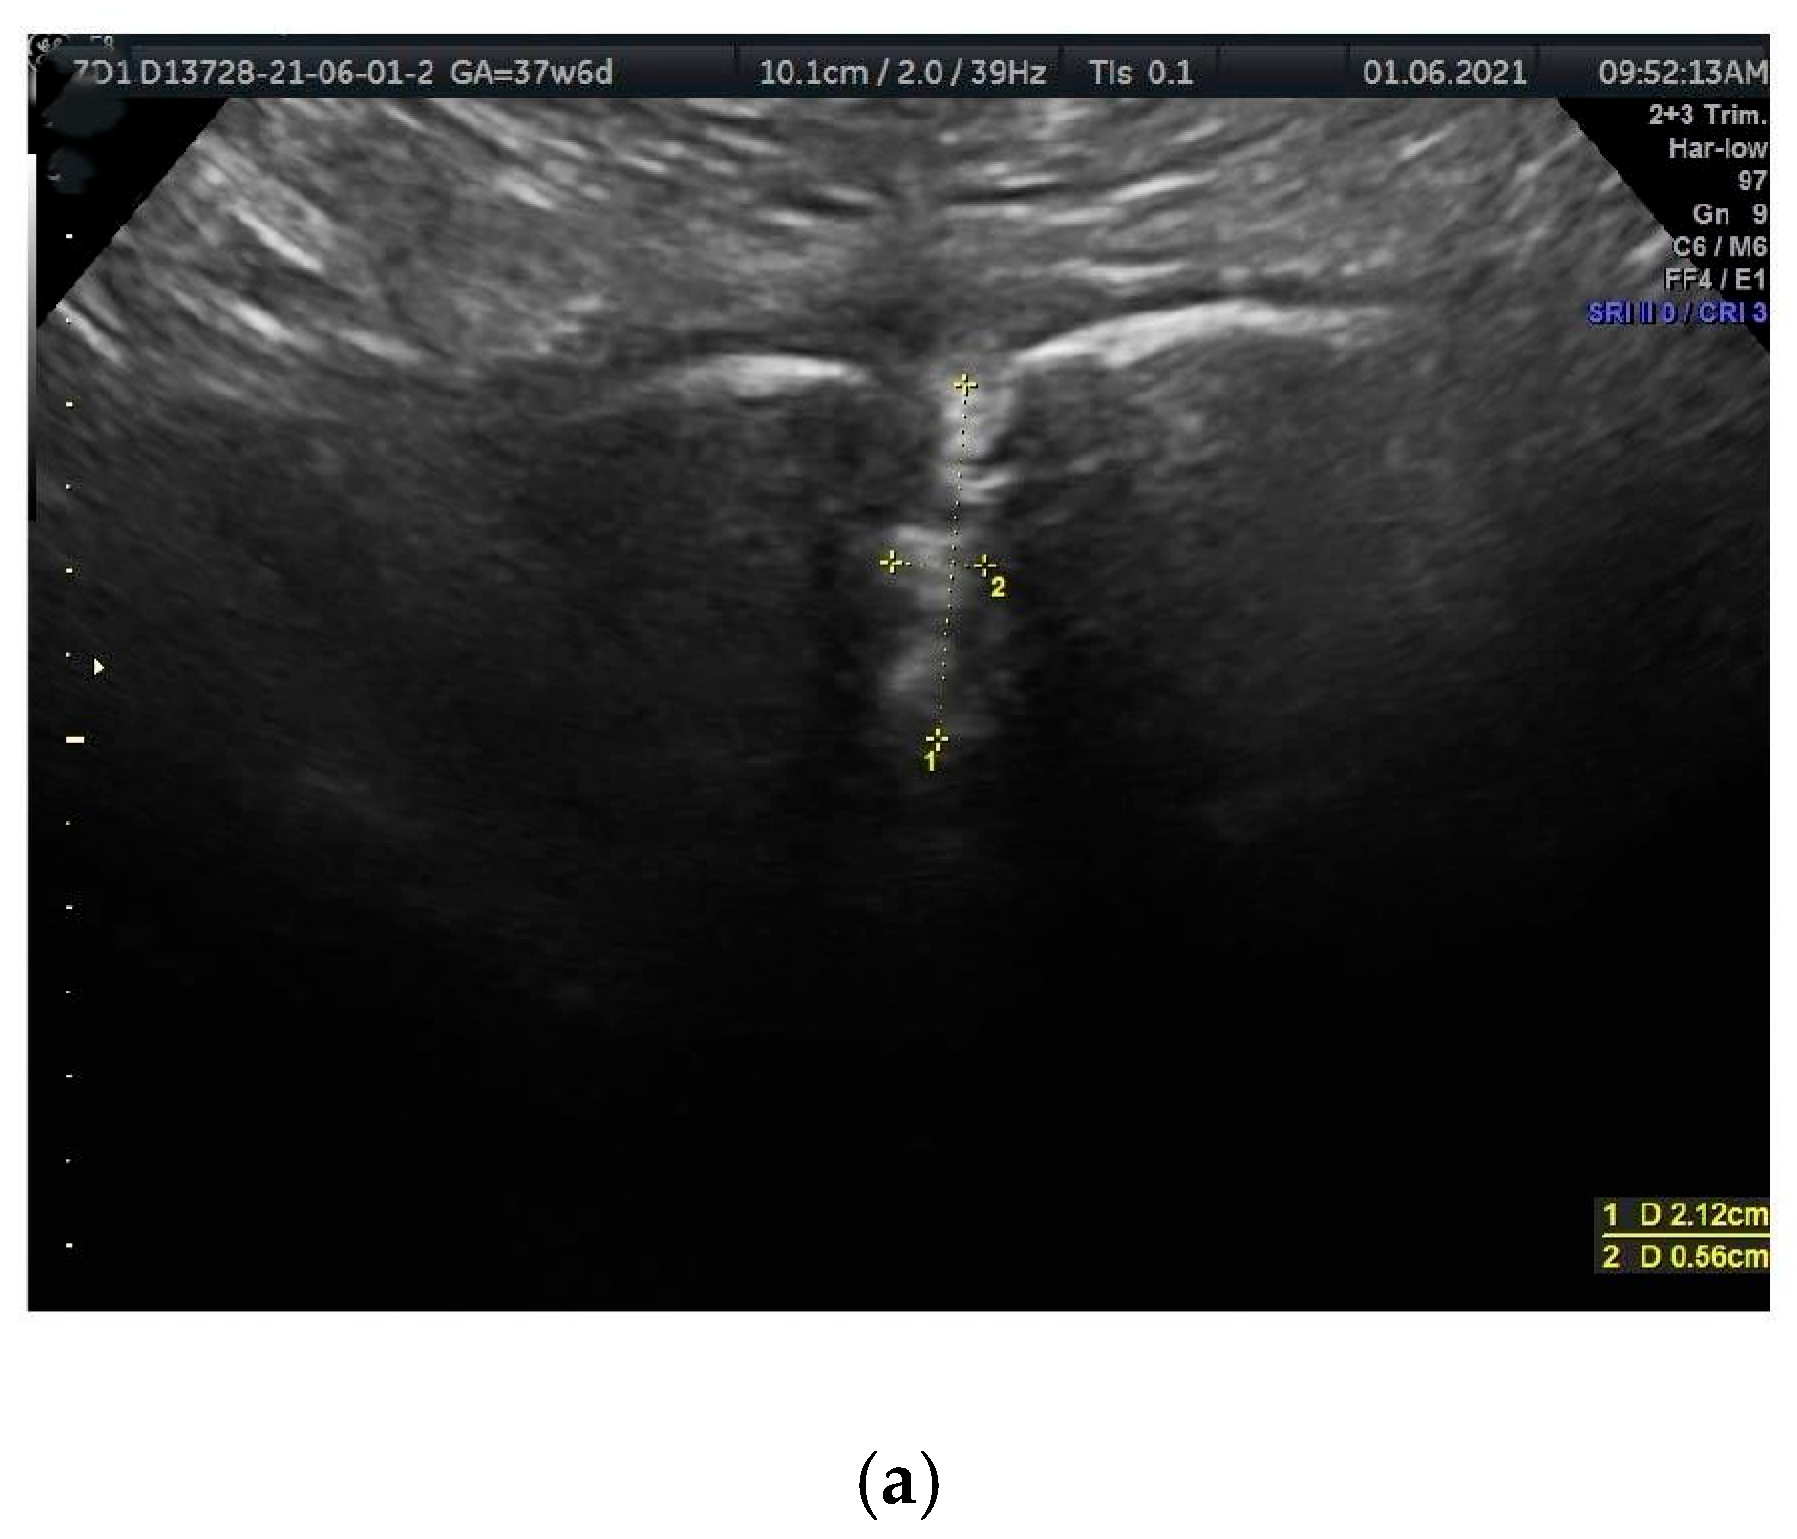

- Intertubercular distance (PT-PT): The span between the right and left PTs.

- PS depth (PSd): The distance between the proximal and distal borders of the PS disc.